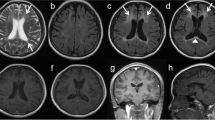

Patients were recruited during routine clinical care at the neurological department of the University Hospital Tübingen, Germany. Information on age, sex, age at symptom onset, and clinical manifestations were collected from all patients, and a detailed neurological examination was performed by a neurologist (Table 1). All individuals underwent cerebral magnetic resonance imaging (MRI) including T2 fluid-attenuated inversion recovery (FLAIR) and diffusion-weighted imaging (DWI) using 3.0 Tesla devices (Fig. 2).

The electrophysiological examination revealed a lesion of the pyramidal tract to the left arm and leg. The magnetic resonance imaging (MRI) of the brain showed supratentorial atrophy and white matter lesions as well as diffusion restriction (Fig. 2A). The neurodegenerative marker NfL was highly increased in serum and CSF (serum: 251 pg/mL, CSF: 19,081 pg/mL; controls [26]: serum: 24.3 ± 3.4 pg/mL, CSF 1052 ± 208.5 pg/mL).

Cerebral magnetic resonance imaging. Magnetic resonance (MR) T2-weighted fluid-attenuated inversion recovery (FLAIR) as well as diffusion-weighted images (DWI) of every patient are depicted. The hallmark features of ALSP in MR imaging are patchy to confluent T2-hyperintensities mainly in the frontoparietal white matter while sparing the temporal lobe, supratentorial global brain atrophy accentuated in the frontal region as well as dispersed foci of restricted diffusion in the periventricular white matter on DWI sequences. All patients had white matter lesions and marked brain atrophy. In five of the patients, diffusion restriction was detected (Patients 1, 4 (circle), 5, 6, 7). All sites of diffusion restriction are hypointense in the apparent diffusion coefficient (ADC) sequence (data not shown)

Over the course of the next 2 years, the gait worsened with parkinsonian features, apraxia became prominent, and cognitive impairment progressed (MoCA 3/30 points). The MRI of the brain showed white matter lesions and global atrophy, but no diffusion restriction (Fig. 2B).

Cerebral MRI showed white matter lesions especially in the frontal lobe as well as global brain atrophy, most pronounced in the frontal lobe. Diffusion restriction was not detected (Fig. 2C). NfL was increased in serum and CSF (serum: 81 pg/mL, CSF: 6840 pg/mL). There were no other abnormalities in the routine CSF analysis and blood tests.

The cerebral MRI showed global atrophy, moderate white matter lesions, especially in the parietal lobe, and one site of diffusion restriction (Fig. 2D). Routine CSF analysis and blood tests were normal. NfL in serum and CSF was strongly elevated (serum: 42 pg/mL, CSF: 7363 pg/mL).

Cerebral MRI at the age of 46 and 47 years showed bilateral white matter hyperintensities on FLAIR sequence, multiple areas of diffusion restriction in subcortical and central white matter on DWI as well as global brain and corpus callosum atrophy (Fig. 2E). NfL in serum and CSF was strongly elevated (serum: 352 pg/mL, CSF: 14,563 pg/mL).

Cerebral MRI showed an advanced neurodegenerative process with significant atrophy of gray and white matter, including the corpus callosum, as well as diffusion restriction (Fig. 2F). Except for protein (72 mg/dl), routine CSF parameters were unremarkable, but NfL was highly increased (9756 pg/ml).

Cerebral MRI showed white matter lesions in the frontal and parietal lobe, global atrophy as well as prominent diffusion restriction (Fig. 2G). NfL in CSF was highly increased (7043 pg/ml).

Genetic testing uncovered a heterozygous variant c.2642C>T, p.Ala881Val in the CSF1R gene (Fig. 1; Table 2). The patient’s mother carried the same variant. Her cerebral MRI revealed extensive confluent hyperintensities in the superior frontal gyri and global brain atrophy accentuated in the frontal region; no diffusion restriction was detected (Fig. 2H). The variant was absent from gnomAD (PM2) and is located in the tyrosine kinase domain of the protein, which is known as a mutational hot spot (PM1). The amino acid alanine at this position (881) is conserved across different species [39] and is classified as deleterious by several in silico prediction programs (PP3). The clinical and MRI phenotype (diffusion restriction) is highly specific for ALSP (PP4). Taken together, the variant was classified as likely pathogenic according to ACMG criteria (PM1, PM2, PP3, and PP4).

Cerebral MRI scans of all seven patients showed frontoparietal white matter lesions and brain atrophy, which are typical features of ALSP [9, 10, 45, 53, 55]. Additionally, diffusion restriction was detected in five of the patients, which is another characteristic finding of the disease [9, 10, 21]. Besides the typical clinical signs and characteristic features in MR imaging, the determination of NfL in serum and/or CSF constitutes the third pillar in the diagnostic workup of ALSP. While NfL serves as a general neuronal biomarker found elevated in various neurological conditions [56], it is exceptionally increased in ALSP [26]. The CSF NfL levels of the patients included in this study ranged from 6840 to 19,081 pg/mL, which significantly exceeds the upper standard value of approximately 1000 pg/mL [26], reflecting the rapid neuronal loss in these patients.